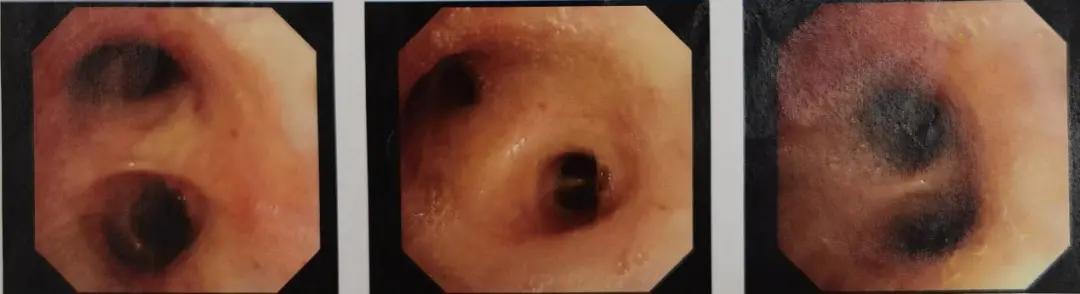

7月14日,患者于当地医院行胸部CT显示两肺多发结节,较4月28日相比有所吸收;纵隔、双侧腋窝小淋巴结;双肺局部少许炎症;脾大,肝内致密影。

图4:胸部CT(2020.07.14)

8月27日于当地医院行胸部CT显示两肺多发结节、絮状影,性质待定,病灶较7月14日相仿;纵隔、双侧腋窝小淋巴结。

图5:胸部CT(2020.08.27)